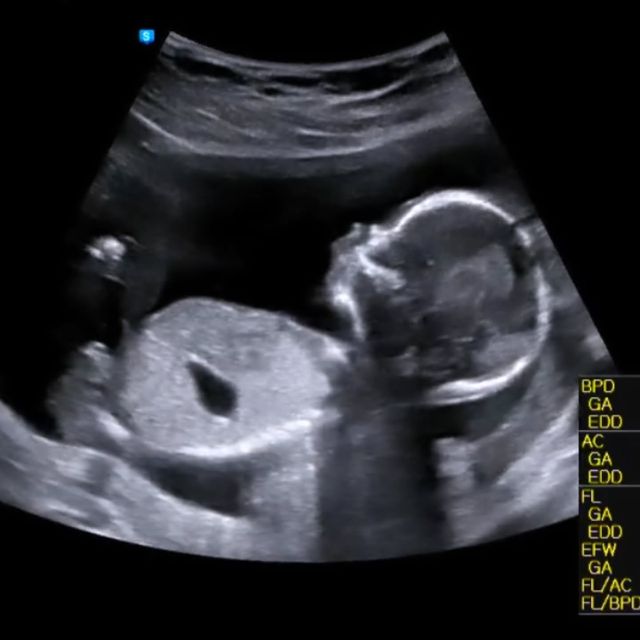

8일 뮤지컬 배우 송문선은 자신의 계정에 초음파 사진을 게시해며 "요 귀여운 아가가 저희에게 찾아와주었다"고 임신 소식을 전했다.

사진=송문선, 김도빈